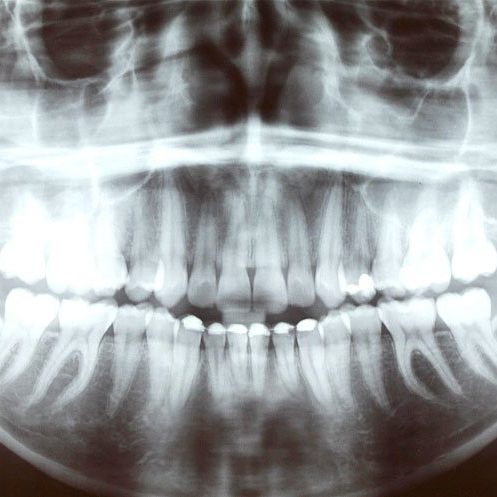

Radiovisiografía

Las radiografías dentales son grandes ayudantes a la hora de detectar e identificar los problemas y percances en las estructuras dentales de nuestros pacientes